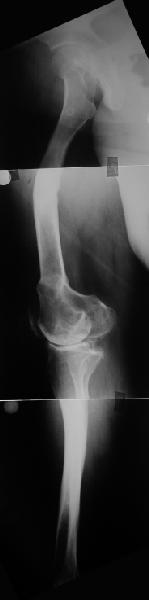

Обратилась дама 57 лет с намерением протезировать коленный сустав. Имется грубая осевая деформация (см. рентгенограммы).

Встает вопрос насчет улучшения оси конечности. Даже с мобилизацией на пртяжении при таком вальгусе малоберцовому нерву может не поздоровиться. Уважаемые коллеги, как лучше провести коррекцию? Какой сегмент, на каком уровне, на какую величину? Что бы Вы исправили до протезирования, что можно оставить и сделать вместе с замещением сустава?